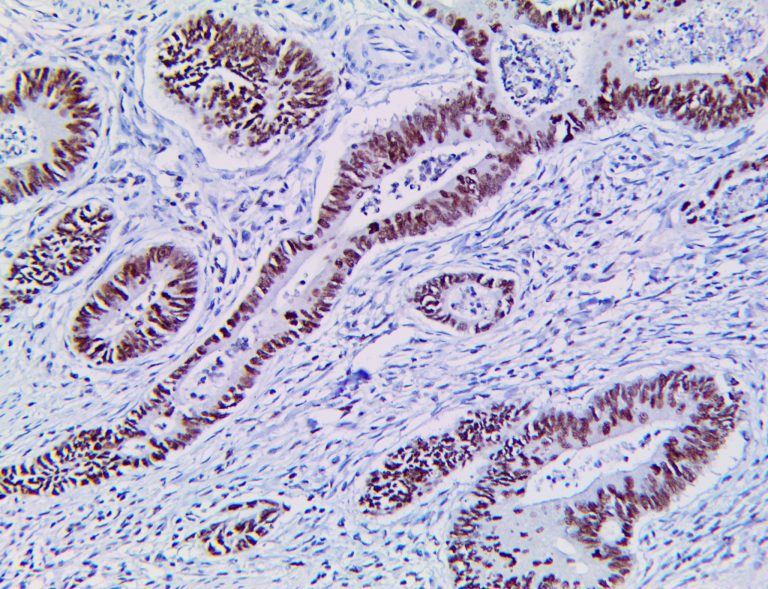

This activation induces inflammatory monocytes to highly express IL-6, starting a localized and then systemic cascade effect that results in hyperproduction of IL-6, which accelerates the inflammatory process. Because IL-6 also increases vascular permeability, excessive levels cause blood vessels to become very leaky. This, along with clotting factors released from vascular endothelial cells, stimulates the coagulation cascade, resulting in microthrombosis (tiny clots), which leads to ischemia and tissue death of the kidney, intestines, heart, liver, brain and extremities.